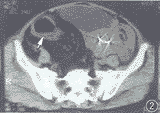

, 百拇医药 CT扫描:盆腔右侧部见多量脂肪密度影,CT值为-77.9 HU,分布以直肠、乙状结肠(右位)周围为主,致肠壁不均匀增厚、肠腔狭窄,并见纤维条索影,显示出“柳条状”结构。膀胱、子宫向左推移(图2,3)。

图2 盆腔右侧部多量脂肪密度影,CT值-77.9 HU,肠壁受侵增厚、肠腔不规则变形。膀胱、子宫向左推移